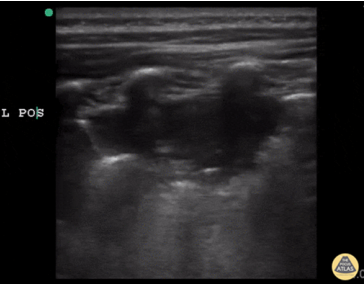

A线的出现代表胸膜线以下含气良好。此时针对呼吸困难的病因,就应考虑是否存在气道病变或血管病变。需要行下肢血管彩超进一步筛查,如果发现血管中有回声团(图2),考虑存在下肢静脉血栓,此时需要警惕肺栓塞的可能。如有条件,可行肺动脉CTA检查;如无条件,可检查凝血功能、心肌标志物、心脏彩超等进行筛查。如果下肢血管彩超没有问题,就要加做PLAPS点(图3),即最常出现胸腔积液、炎性变之处,若此处正常,考虑可能是气道疾病,若出现胸膜下斑片影、实变影,考虑肺炎可能。(3)不论有无胸膜滑动征,如果在患者一侧以A线为主,另一侧以B线为主(AB profile)(图4),考虑为肺炎;若超声有实变征象(C profile)(图5),则更支持肺炎的诊断。图4 一侧为A线,另一侧为B线(AB profile)(4)如果胸膜滑动征消失,且观察到B线(B’ profile)(图6),此种情况考虑肺炎。(5)如果胸膜滑动征消失,且双肺表现为A线,称为A'profile。